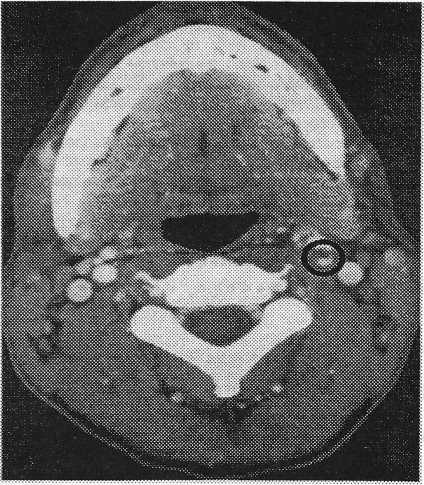

35-летний солдат в первый же день инсульта был переведен в нашу клинику с заключением о “большом сгустке крови” в левой внутренней сонной артерии, по данным дуплекс-сонографического исследования, были отмечены левосторонний синдром Горнера, афазия, апраксия и атаксия правой руки. В день, предшествовавший инсульту, больного беспокоили сильные головные боли с левой стороны, в связи с которыми он принял 1 г аспирина. Ангиография показала закупорку левой внутренней сонной артерии в 2 см дистальнее развилки. Цветная дуплекс-сонография, казалось, подтверждала закупорку сосуда. Тем не менее КТ мягких отделов шеи с контрастным веществом была типична для разрыва сосуда с минимальным остаточным просветом. Во внутричерепной области КТ головного мозга выявила ареал пониженной плотности в задней области кровоснабжения внутренней черепной артерии (рис. 1).

Рис. 1. Наблюдение 2. Компьютерная томограмма мягких тканей шеи с контрастным веществом. Диссекция левой внутренней сонной артерии (отмечено кругом).